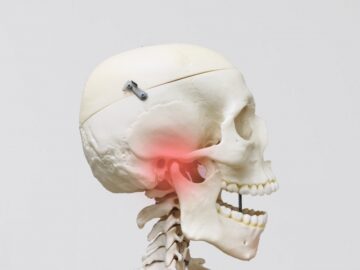

顎顔面矯正治療とは、歯並びだけでなく噛み合わせや顎関節を考慮して行う矯正治療のことです。顎顔面矯正治療により、顎関節症の緩和や鼻づまりの改善効果も期待できると言われています。主に、小児期に行い、見た目をよくするだけではなく、顎の骨や顔の骨格を正しい形に導きます。

歯並びの悪い原因としては顎の急な成長によるものが多く、装置で顎を広げる事で歯が綺麗に並ぶスペースを確保します。

上顎の骨には繋ぎ目が存在しており、そこで左右二つの骨に分かれています。急速拡大装置を上顎に固定して装置の中央にあるネジを回すことで繋ぎ目を広げ、徐々に上顎の骨の変えていきます。そうすることで、顎の骨が正しい形に成長していくよう促され、永久歯を正しい位置で生えるように誘導できます。

急速拡大装置で上顎の拡大が進むと、下顎の骨も調整する必要が出てきます。その際に使う装置がリンガルアーチです。下顎の骨は上顎の骨と作りが違います。下顎はひとつの骨で構成されているので、上顎と同じように拡大させることができません。内側に傾いている歯を起こすようにして歯列部分だけを拡げていきます。この装置も固定式の装置となっており、歯の裏側に装着しますので目立たない見た目となっています。

上顎の拡大と下顎の歯の調整が進むと、機能的矯正装置であるアクチバトール(FKO)という装置を使用します。アクチバトール(FKO)は着脱式の矯正装置で、下顎を適切な位置へ誘導します。 顎の位置、形態が改善し、舌、口唇の位置、使い方が改善すれば、自然に歯の位置が変わって歯が綺麗に並ぶようになります。

顔やお口回りの写真撮影・顎の骨や頭蓋骨全体のレントゲン撮影・噛み合わせの型取り・顎関節や呼吸の仕方チェック等を行い、矯正治療に必要な情報を収集するために、検査を行います。